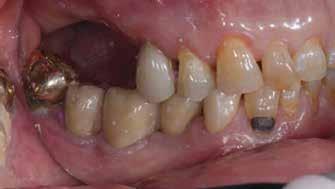

Esetismertetés

Az 50 éves nőpáciens az alsó és felső állcsont területén egyaránt panaszt (fájdalom, ráharapási érzékenység) okozó, harmadfokban mozgatható fogak miatt jelentkezett rendelőnkben. Az általános anamnézisben említést érdemlő betegség, műtét nem szerepelt. Az elvégzett klinikai és radiológiai vizsgálatok (1–2. ábra) alapján fogai reménytelen parodontális státusúnak bizonyultak, hosszú távon sem megtartásuk, sem protetikai célú felhasználásuk nem volt lehetséges. A parodontális prognózis a fogak eltávolításának abszolút indikációját jelentette. Ezáltal mindkét állcsontban teljes foghiány kialakulásával kellett számolnunk. A protetikai szemléletű, „visszafelé” tervezés elveit követtük a hosszú távú funkcionális, esztétikai siker és szöveti stabilitás elérése érdekében: mindkét állcsontban overdenture típusú fogpótlás készítése mellett döntöttünk. A megfelelő implant-protetikai rehabilitáció alapja az implantátumok megfelelő pozicionálása. A korábbi parodontális kórfolyamat következtében a processus alveolarisokat érintő eredendő csontdeficittel kellett számolnunk, amelyet tovább súlyosbíthatott volna a hagyományos extrakciós technikát követő involúciós atrófia. Ezért a páciens kivizsgálása és megfelelő előkészítése után a fog eltávolításával egy időben PRF

27 VI. ÉVFOLYAM – 2023. 4. SZÁM

Sticky Tooth segítségével kivitelezett alveolus prezerváció mellett döntöttünk, a megfelelő csontos és mukogingivális gyógyulás minőségi és mennyiségi elősegítése érdekében. A PRF készítmény mennyiségét, minőségét, kezelhetőségét és hatékonyságát jelentősen befolyásolják a páciens laborértékei, ezért kezelési protokollunk szerint a műtétet megelőzően minden esetben laborvizsgálatot végzünk (hemoglobin: 134 g/liter, hematokrit: 0,43, fehérvérsejt: 6,6 G/liter, CRP: 13,60 mg/liter, vércukor: 6,2 mmol/liter, összkoleszterin: 7,00 mmol/liter, triglicerid: 1,08 mmol/liter, HDL koleszterin 2,57 mmol/liter, LDL koleszterin 1,12 mmol/liter), D3 vitamin: 117,5 nmol/liter).

A fogak eltávolítása és az alveoláris csont megőrzésének és regenerációjának segítése céljából elvégzett augmentáció altatásban történt. Óvatos, atraumatikus extrakciót követően eltávolítottuk a parodontális és periapikális gyulladásos folyamatok eredményeként jelen lévő sarjszövetet. A bukkális csontfal hiánya és a tervezett vertikális augmentáció miatt indokolt membrántechnika megfelelő kivitelezése céljából a felső állcsonton mukoperioszteális lebenyt képeztünk (3–4. ábra). Az alveolus prezervációt Sticky Tooth, PRF és titánerősítésű teflon (PTFE-Ti) membránok segítségével végeztük el, a J. Choukroun által megadott vérvételi és centrifugálási protokoll (28) elveinek betartásával: kizárólag Process for PRF Duo Quattro System eszközöket, centrifugát, vérvételi egységet és csöveket, a membránok előállításához PRF Boxot használtunk. Az A-PRF és S-PRF csöveket a PomPac eljárásnak megfelelően 4 Celsius-fokra előhűtöttük. Az eltávolított fogak makroszkópos tisztítását és darabolását nagy fordulattal (300 000 RPM) fogászati turbinába helyezett gyémántfúróval végeztük, majd Tooth Transformer™ berendezéssel, annak gyári reagens rendszerével kezelt őrleményt nyertünk. A Sticky Tooth készítmény előállítása a PRF készítmény és az őrlemény